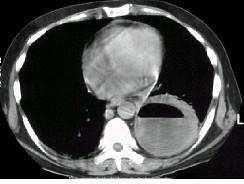

问题 男,36岁,胸痛半月伴发高热,胸片发现占位性病变,CT检查如图,最可能的诊断为 ( )

选项 A.左下肺肺脓肿 B.左下肺癌并空洞形成 C.左侧胸腔积脓 D.左下肺囊肿 E.左下肺肺炎

答案 A